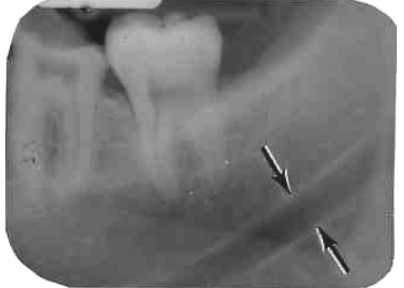

31. What arrow shows?

32. What is showing by the arrow?

33. What is showing by arrow?